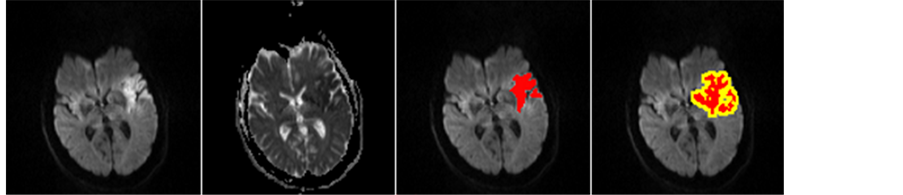

The highest Dice is achieved from feature selection using on MI algorithm with 15 features on SVM. The mean Dice, sensitivity and specificity are 0.763 ± 0.121, 76.08% ± 14.8%, 99.95% ± 0.098% respectively. Two slices with good and bad segmentation are shown in Figure 6.

Figure 6. Segmentation of two DW axial slices with high (a) and low (b) Dice coefficient, red for ground truth infarcts and green for segmented infarcts. (a) Good segmentation; (b) Bad segmentation.